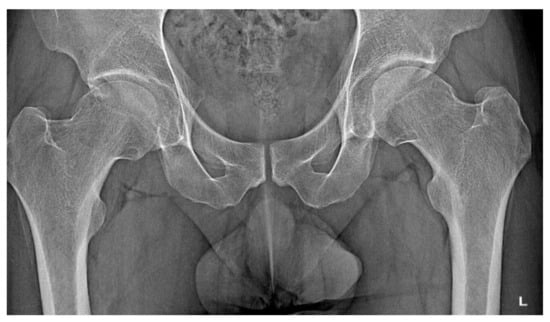

3.1. Case 1: OO Masking as Femoroacetabular Impingement (FAI)

3.6. Case 6: OO Masking as Chronic Hip Arthritis